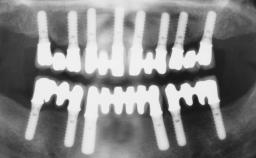

Rehabilitating an Edentulous Maxilla with a Fixed Dental Prosthesis Following Provisional Immediate Loading

This case features the flapless computer-guided placement of 7 bone-level implants, distributed to provide maximal support for the prosthetic framework. A rigid one-piece metallic framework was utilized as an interim restoration to reduce the risk of fracture associated with this prosthetic design. As part of the clinical examination, the SAC Assessment Tool was used, resulting in a surgical and restorative risk classification as “complex”.

# of Implants 7